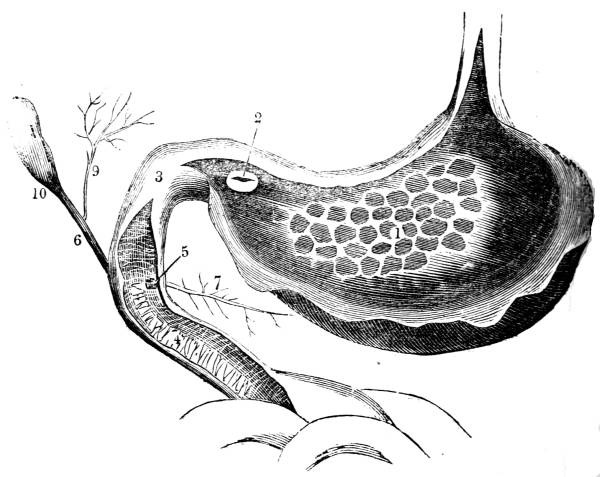

Fig. CXXXVIII.—

View of the Bronchial Tubes terminating

in Air vesicles.

Fig. 138.Fig. 139.

External view.—1. Bronchial tube. 2. Air vesicles. Fig.

139. The same laid open.